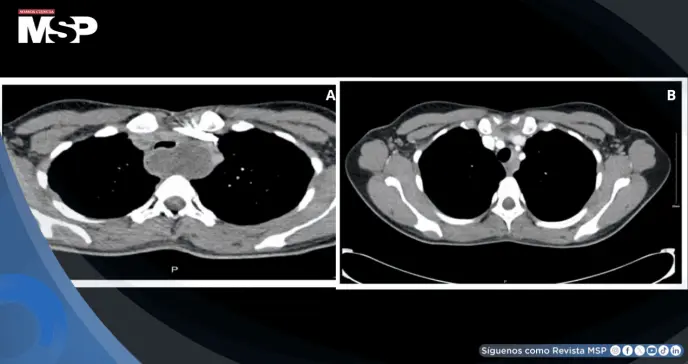

Se realizó una angiografía pulmonar por tomografía computarizada que, si bien descartó enfermedad tromboembólica, identificó un hallazgo incidental relevante: una lesión quística de aproximadamente 5 centímetros localizada en el mediastino superior, específicamente en la región posterior a la tráquea, desplazando el esófago hacia anterior sin evidencia de compresión o invasión de estructuras adyacentes.

El seguimiento imagenológico programado se realizó seis semanas después del parto mediante tomografía computarizada de tórax.

Los resultados fueron notables y sorprendentes: la lesión quística había experimentado una reducción significativa en su tamaño, midiendo ahora apenas 1 centímetro, lo que representaba una disminución del 80% respecto a su tamaño inicial.